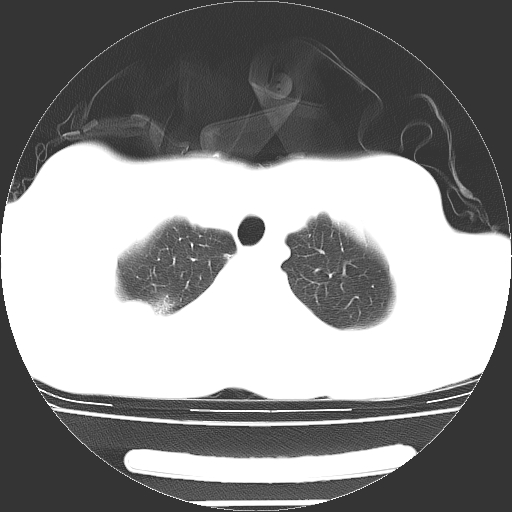

以下是引用dyqct在2008-4-29 8:43:00的发言:[br][br] 支持右侧胸腔包裹性积血。闭式引流管是不是插的太深了?

以下是引用zjzjr在2008-4-29 14:11:00的发言:[br]支持右侧胸腔包裹性积血。闭式引流管是不是插的太深了?胸腔引流,引流管快进入纵隔了.